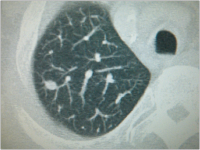

Thorax-CT

Abbildung 1: Thorax-CT mit solitärer Metastase im linken Lungenunterlappen.